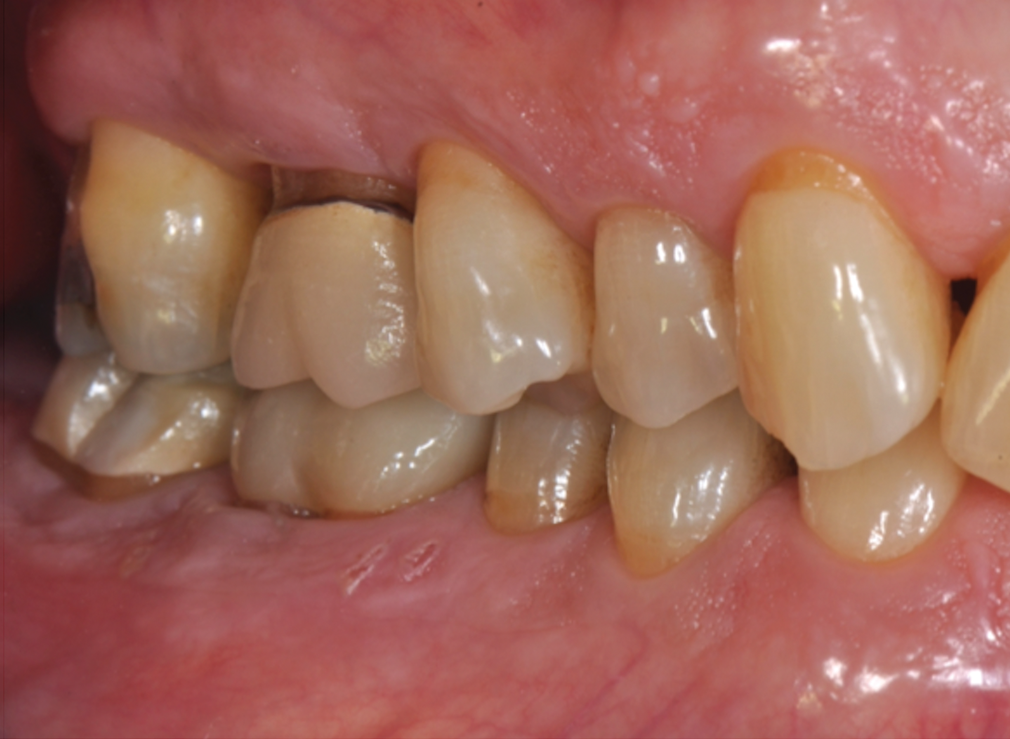

Periodontal examination revealed generalized BOP and PDs up to 9 mm in the maxillary and mandibular molars with multiple furcations in each molar (Figure 2 through Figure 7). He presented with class I mobility in many posterior teeth and class II mobility in teeth Nos. 3 and 9 (maxillary right first molar and maxillary left central incisor, respectively). The periodontist decided to score tooth No. 3 for the PRS, as this was the most periodontally involved molar that was planned to be treated and maintained (Figure 2 and Figure 8). This tooth (maxillary right first molar = score 1) presented with probing depths of 7 mm (score 1); three total furcation invasions (score 3) (mesial [degree II furcation], buccal [degree I furcation], and distal [degree II furcation]); and a class II mobility (score 2). The total PRS for tooth No. 3 was 8, representing a "guarded" prognosis. Based on this score, the likelihood of not losing any teeth to periodontal disease for 15 years was 81%, and for 30 years the likelihood was just 56% (Figure 9).7

Fig 2. Pretreatment views: right lateral (Fig 2), frontal (Fig 3), and left lateral (Fig 4). Note: The maxillary right first molar (tooth No. 3) (Fig 2) would be identified as the most periodontally involved molar that was planned to be maintained.

Figure 2

Fig 10. Clinical views at 4-year follow-up: right lateral (Fig 10), frontal (Fig 11), and left lateral (Fig 12). There was significant reduction in PD, BOP, and mobility.

Figure 10